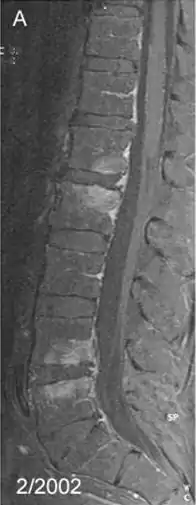

Spondylitis due to Tropheryma whipplei: Contrast-enhanced, T1 weighted fat suppressed magnetic resonance imaging demonstrating contrast enhancing lesions of spondylitis in the first (L1) and second (L2), as well as fourth (L4) and fifth (L5) lumbar vertebra, sparing the intervertebral discs | |